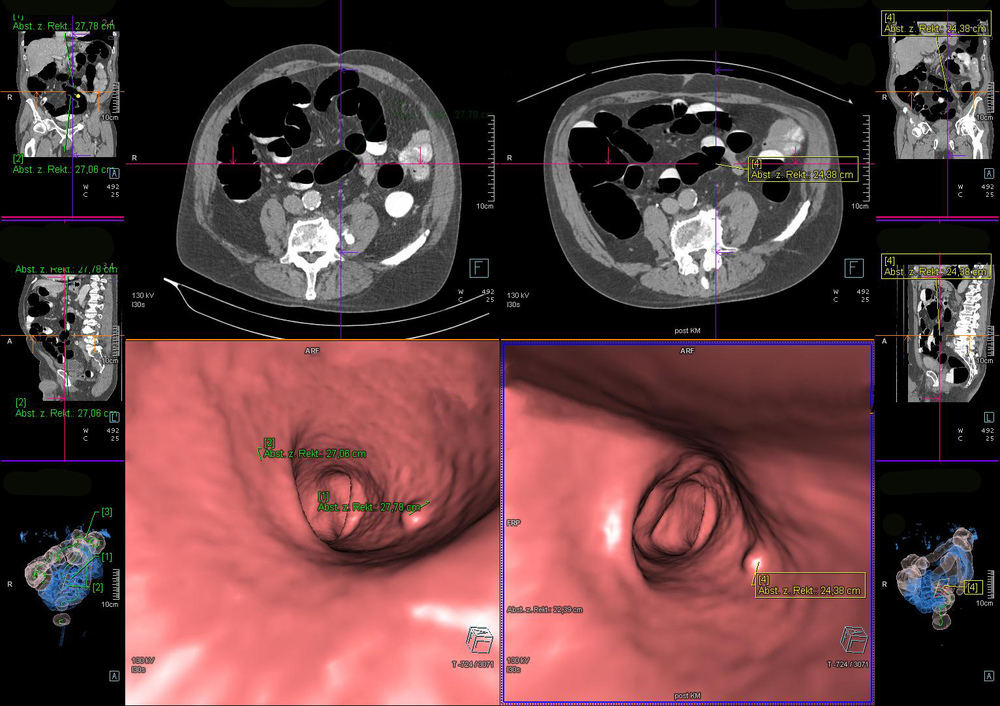

Bei der virtuellen Darmspiegelung erstellen die RadiologInnen mithilfe eines Computertomographen (CT) ein 3-D-Modell vom Darm der PatientInnen. Auf dem Monitor können die RadiologInnen sich dann auf einen virtuellen „Flug“ durch den Darm begeben und die Schleimhautoberfläche von allen Blickwinkeln und -richtungen betrachten. Im Gegensatz zur herkömmlichen Koloskopie kann die virtuelle Koloskopie auch die Darmwand sowie andere Organe des Bauchraumes darstellen.

Abbildung eines 3-D-Modell eines Darmes